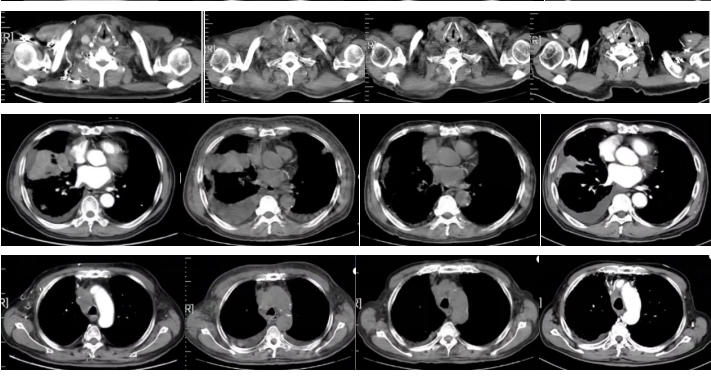

图3

2022-09-17胸部平扫CT:恶性肿瘤维持性化学治疗后,较2022-7-20胸部CT旧片,右肺中叶占位(7.3×4.4cm)缩小;双肺部分结节增大;纵隔及右肺门淋巴结缩小;主动脉左侧旁(2-22)淋巴结稍增大:右侧胸腔积液增多;左侧新增胸腔积液;胸壁水肿增厚,双侧腋窝小淋巴结,请结合临床;余未见显著变化。附见,胰尾较前稍增粗:肝S4段新增低密度小结节,请结合腹部相关检查。

疗效评价:SD。

2022-11-16胸部平扫CT:恶性肿瘤维持性化学治疗后,较2022-9-16日胸部CT,右肺中叶占位(2.2×1.9cm)缩小;双肺大部分结节消失;右侧胸腔积液减少,左侧胸腔积液消失;纵膈及双侧腋窝淋巴结缩小;扫描层面内肝脏结节本次未见明确显示,胰腺结节缩小;余较前变化不大。

疗效评价:PR。